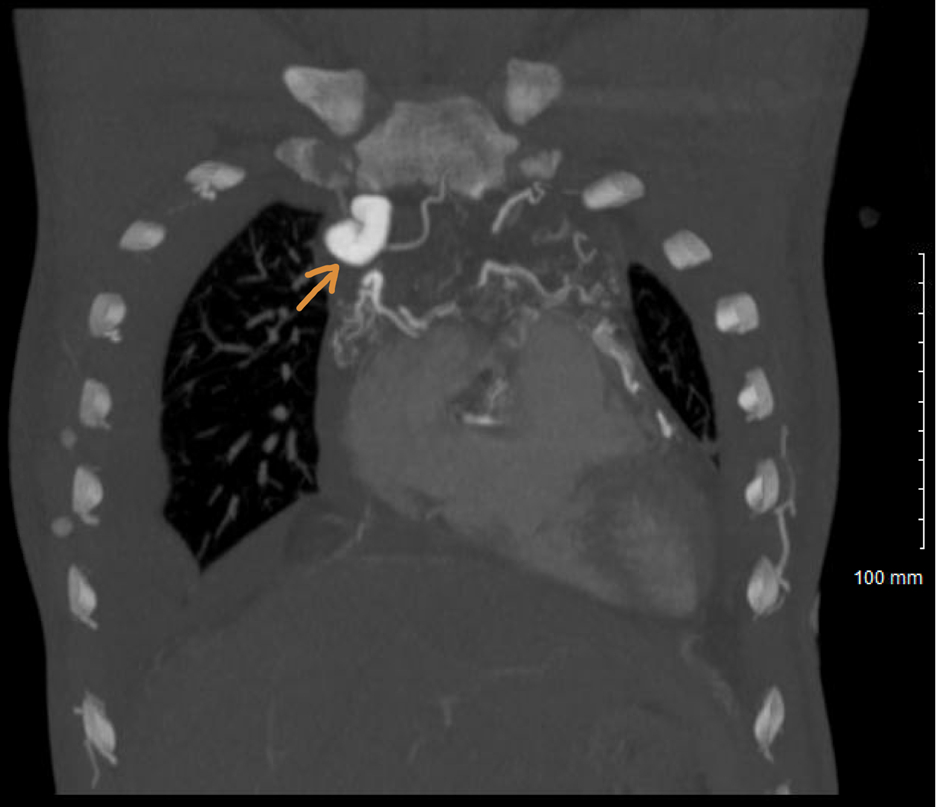

CT angiography revealed chronic right SVC occlusion with extensive venous collaterals draining into the pulmonary veins (Figure 2), mimicking a PLSVC with unroofed coronary sinus. The SVC occlusion likely resulted from years of central venous catheterizations for dialysis. Thus, common sequelae of chronic illness produced a pattern resembling rare congenital anomalies.